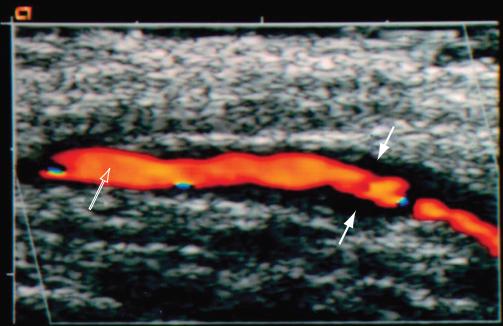

GCA病人长箭头指红肿的动脉;短箭头指血管活检遗留瘢痕

GCA的颞动脉超声:实心箭头所指晕轮征;空心箭头指血管腔